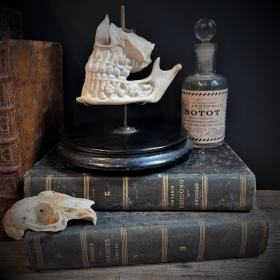

Human jaws in porcelain mounted on a blackened wooden base

Anatomical dental model for dentists

Human jaws in porcelain mounted on a blackened wooden base - Napoleon III type

Anatomical dental model for dentists of the lower skull from the 19th century

What is original is that the whole piece is made of unglazed porcelain, which is called biscuit, except for the teeth which are well glazed.